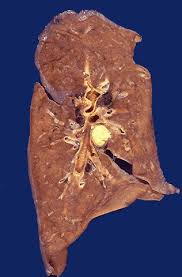

3. Caseous necrosis

All of the cells in an area die, the tissue architecture is obliterated, and they turn into a crumbly ("friable"), readily-aerosolized powder.

A distinct form of coagulative necrosis seen in mycobacterial infections (e.g., tuberculosis), or in tumor necrosis, in which the coagulated tissue no longer resembles the cells, but is in chunks of unrecognizable debris. Usually there is a giant cell and granulomatous reaction, sometimes with polys, making the appearance distinctive.

Gross appearance of caseous necrosis in a hilar lymph node infected with tuberculosis. The node has a cheesy tan to white appearance. Caseous necrosis is really just a combination of coagulative and liquefactive necrosis that is most characteristic of granulomatous inflammation.

Found in granulomatous inflammation; manifestation of partial immunity of interaction T-Lymphocyte, macrophage, and cytokines associated with tubercolosis. Architecture is not preserved but tissue is not liquefied. Grossly soft and cheeselike. Histologically amorphous and acidophilic.